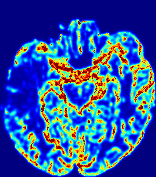

4.3.2 Diffusion Imaging via Advection-Diffusion

Slice #1Slice #2Slice #3Slice #4Slice #5Slice #6Dgtsuperscript𝐷gtD^{\text{gt}}Refer to captionRefer to captionRefer to captionRefer to captionRefer to captionRefer to captionDestsuperscript𝐷estD^{\text{est}}Refer to captionRefer to captionRefer to captionRefer to captionRefer to captionRefer to captionRefer to caption0.300.300.300.240.240.240.180.180.180.120.120.120.060.060.060.000.000.00(mm2/s)𝑚superscript𝑚2𝑠(mm^{2}/s)𝐕est𝟐subscriptnormsuperscript𝐕est2\|\bf{V}^{\text{est}}\|_{2}Refer to captionRefer to captionRefer to captionRefer to captionRefer to captionRefer to captionRefer to caption0.00300.00300.00300.00240.00240.00240.00180.00180.00180.00120.00120.00120.00060.00060.00060.00000.00000.0000(mm/s)𝑚𝑚𝑠(mm/s)

Figure 15: PIANO identifiability testing: diffusion imaging via advection-diffusion. Top row shows Dgtsuperscript𝐷gtD^{\text{gt}} used for simulating ground truth pure diffusion. Rows below show the estimated Destsuperscript𝐷estD^{\text{est}} and 𝐕est2subscriptnormsuperscript𝐕est2\|{\bf{V}}^{\text{est}}\|_{2} on corresponding slices. Note that the plotted value scale for 𝐕est2subscriptnormsuperscript𝐕est2\|{\bf{V}}^{\text{est}}\|_{2} is 0.01 of that for Dgtsuperscript𝐷gtD^{\text{gt}} and Destsuperscript𝐷estD^{\text{est}}.

Similarly, we test the behavior of PIANO when estimating both advection and diffusion from a pure diffusion-driven process. The goal is to determine if PIANO is able to recognize that there is only diffusion governing the given concentration time-series. We use the same ‘Diffusion Imaging’ data simulation of Sec. 4.2.1 as the concentration dataset, PIANO estimates both velocity 𝐕estsuperscript𝐕est{\bf{V}}^{\text{est}} and diffusivity Destsuperscript𝐷estD^{\text{est}}. Estimation results in Fig. 15 confirm PIANO’s identifiability again: the estimated 𝐕est2subscriptnormsuperscript𝐕est2\|{\bf{V}}^{\text{est}}\|_{2} is almost invisible compared to Destsuperscript𝐷estD^{\text{est}}, even plotted with a 1%percent11\% value range compared to that for Destsuperscript𝐷estD^{\text{est}}. On the other hand, Destsuperscript𝐷estD^{\text{est}} achieves comparable estimation performance as ‘Diffusion Imaging via Diffusion’ in which PIANO predicts Destsuperscript𝐷estD^{\text{est}} alone (shown in Fig. 13).